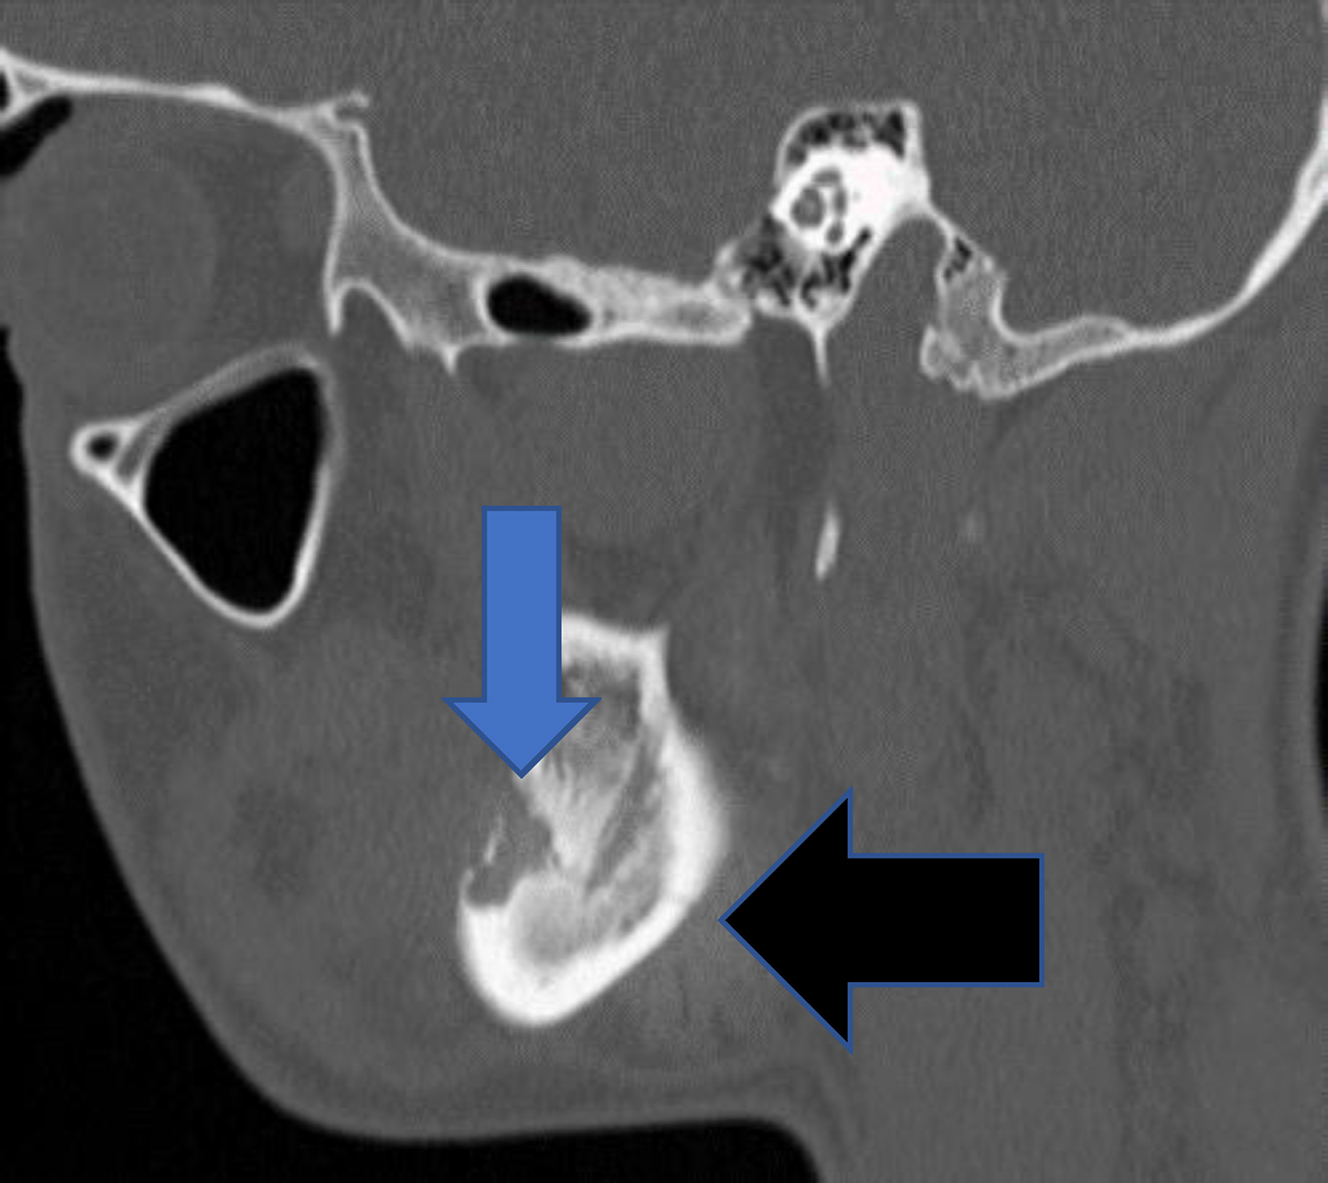

Once a mandible fracture is suspected based on history and physical examination, there are several diagnostic imaging modalities that can be used based on availability. Panorex plain films (orthopantomogram) in combination with a posterior-anterior plain film will provide two views of the mandible which would show an MAF, while a panorex radiograph alone may miss a posterior fracture. However, the equipment to obtain panorex views tends to be of limited availability in the hospital-based emergency room setting, and thus, a mandible series of radiographs or CT have been adopted as the gold standard. A mandible series includes three views: posteroanterior, oblique, and lateral. However, these three views may not clearly visualize the condyles. CT imaging has become the modality of choice and has been shown to have a 100% sensitivity to detect all fractures of the mandible. CT also has the advantage of assessing the involvement of tooth roots in the line of fracture, the presence of severe dental disease, and also screens for other facial fractures. Additionally, CT scans can be used to produce three-dimensional reconstruction which can help with operative planning or the selection of patient-specific plating if necessary.

Currently, the Champy technique for osteosynthesis is used preferentially for noncomminuted fractures of the mandibular angle. The Champy technique was popularized by Maxime Champy in the 1970s. Dr. Champy recognized that the angle of the mandible had certain characteristics that were favorable with regard to using a load-sharing engineering concept with regard to mandibular fixation. Load sharing is an engineering technique where forces caused by mandibular function will be counteracted by placing plates with monocortical screws in such a way that tensile or distractive forces are obviated while beneficial compressive forces are strategically promoted. This is in contrast to load-bearing repairs, whereby all forces at play on a functioning mandible will be overcome and neutralized by thick and rigid plates that have absolutely no mobility and use bicortical screw placement. The Champy technique uses optimal plate placement along Champy’s lines using monocortical screws that counteract tensile forces that occur during mandible function while allowing compressive forces to be controlled in the pursuit of bone healing ( Fig. 2 ). By using monocortical miniplates to counteract tensile forces, smaller and thinner plates can be used. Less surgical exposure and periosteum stripping is required, and less bone drilling is necessary. However, the Champy technique is not a rigid technique. It does allow some movement at the fracture site after repair. The Champy technique also relies on bone surface area contact to help stabilize the fracture, and therefore, comminuted fractures are not ideal for the technique ( Fig. 3 ). One other factor makes the angle an opportune place for utilization of this technique: the fact that angle fractures are actually behind the dentate portion of the mandible. Similar to sagittal split osteotomy surgery, the location of the angle fracture in this retro-occlusal zone allows leeway with regard to the precision of the final osteosynthesis as it relates to postoperative occlusion.